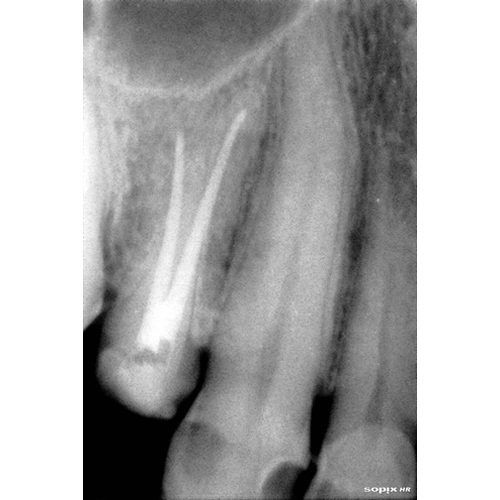

Nuestros procedimientos son realizados bajo magnificación microscópica